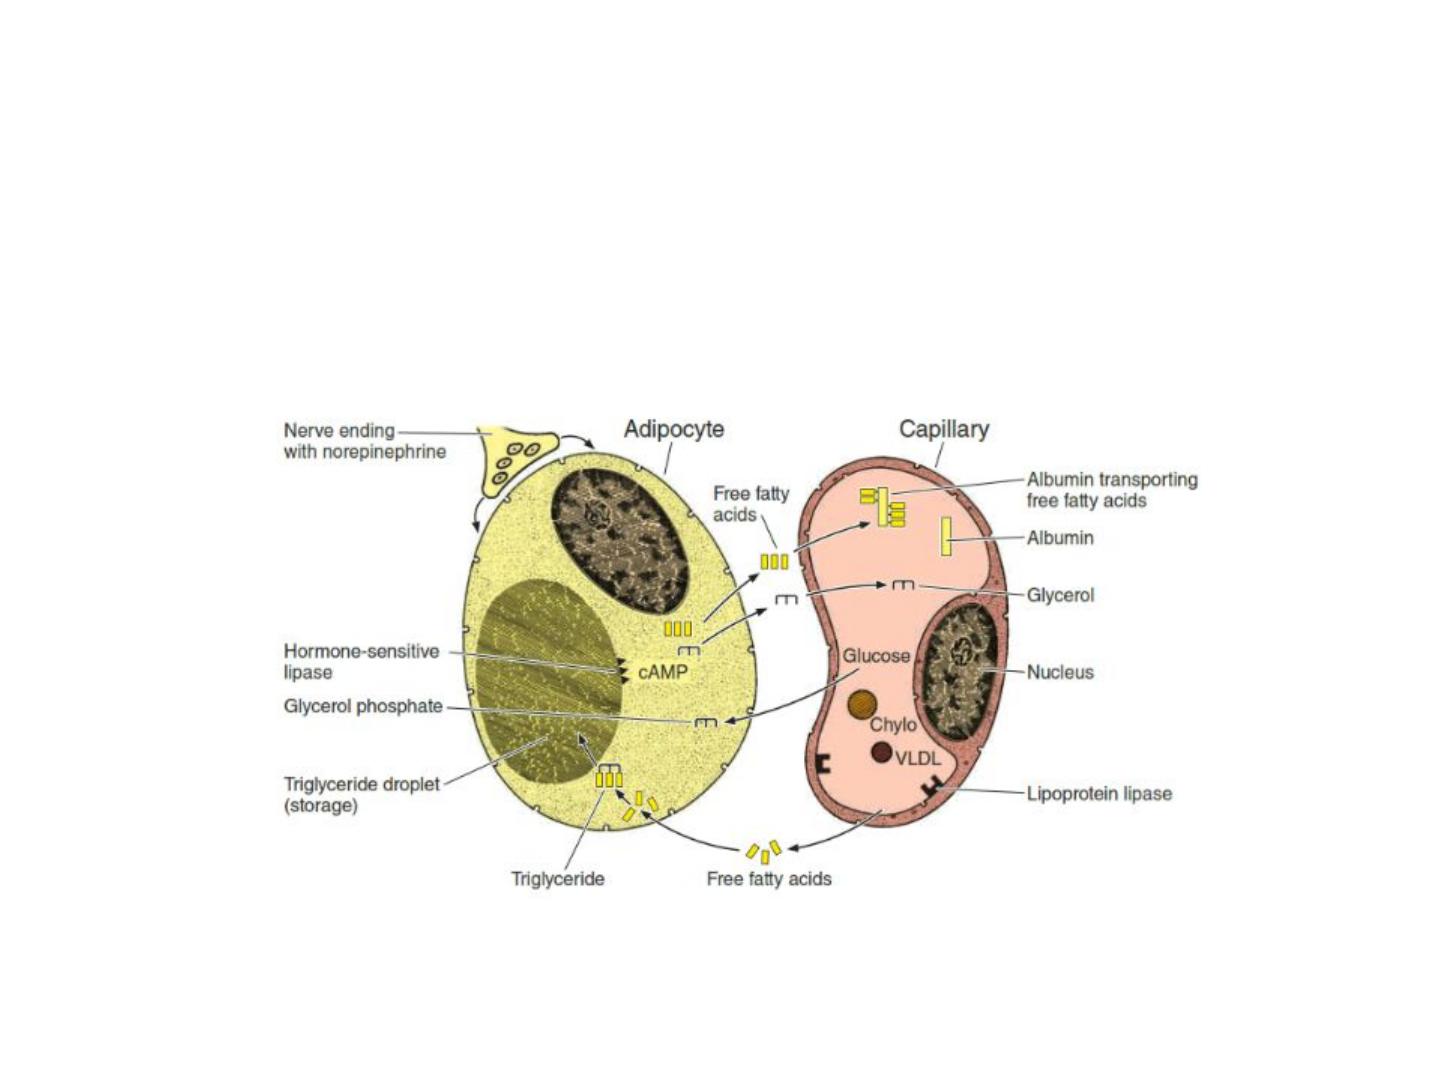

Storage & Mobilization of Lipids

Triglycerides stored by cells of white adipose tissue can be derived from dietary fats

brought to adipocytes as circulating chylomicrons, from triglycerides synthesized in the

liver and transported as very-low-density lipoproteins (VLDLs), and by the local synthesis

of free fatty acids and glycerol from glucose. Chylomicrons (Gr. chylos, juice + micros,

small) are small particles of variable size, up to 1200 nm in diameter, formed Triglycerides

are transported by blood and lymph from the intestine and liver in lipoprotein complexes

known as chylomicrons (Chylo) and VLDLs. In the capillary endothelial cells of adipose

tissue, these complexes are partly broken down by lipoprotein lipase, releasing free fatty

acids and glycerol. The free fatty acids diffuse from the capillary into the adipocyte,

where they are esterified to glycerol phosphate, forming triglycerides that are stored in

the lipid droplet until needed. Norepinephrine from nerve endings stimulates the cyclic

AMP (cAMP) system, which activates hormone-sensitive lipase to hydrolyze the stored

triglycerides to free fatty acids and glycerol. These substances diffuse into the capillary,

where the fatty acids bind albumin for transport throughout the body for use as an

energy source.

Figure 3: lipid storage and mobilization from adipocyte

Low levels of glucose in the blood trigger the mobilization of triglycerides through

the action of epinephrine and glucagon.

cAMP pathway activate hormone sensitive lipase to cause hydrolysis of triglycerides

into glycerol and FFA.

Mobilization of Triglycerides Stored in Adipose Tissue